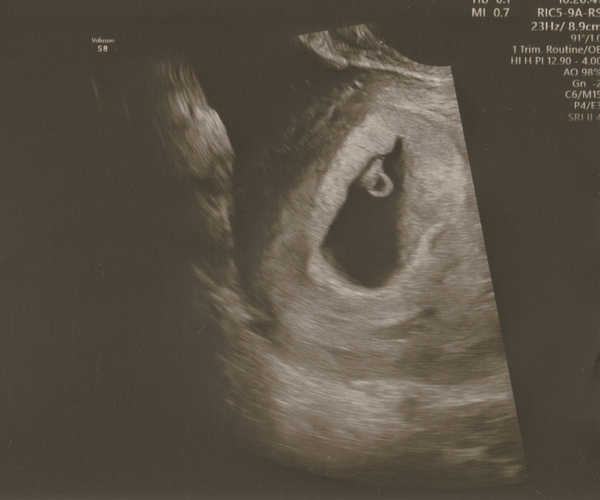

I had mine today at 6 weeks 5 days, measuring spot on. We saw a little heart beat. It was all so surreal in the loveliest possible way.

I've attached a picture. So you should see something like this or more around the 7 week 2 day mark